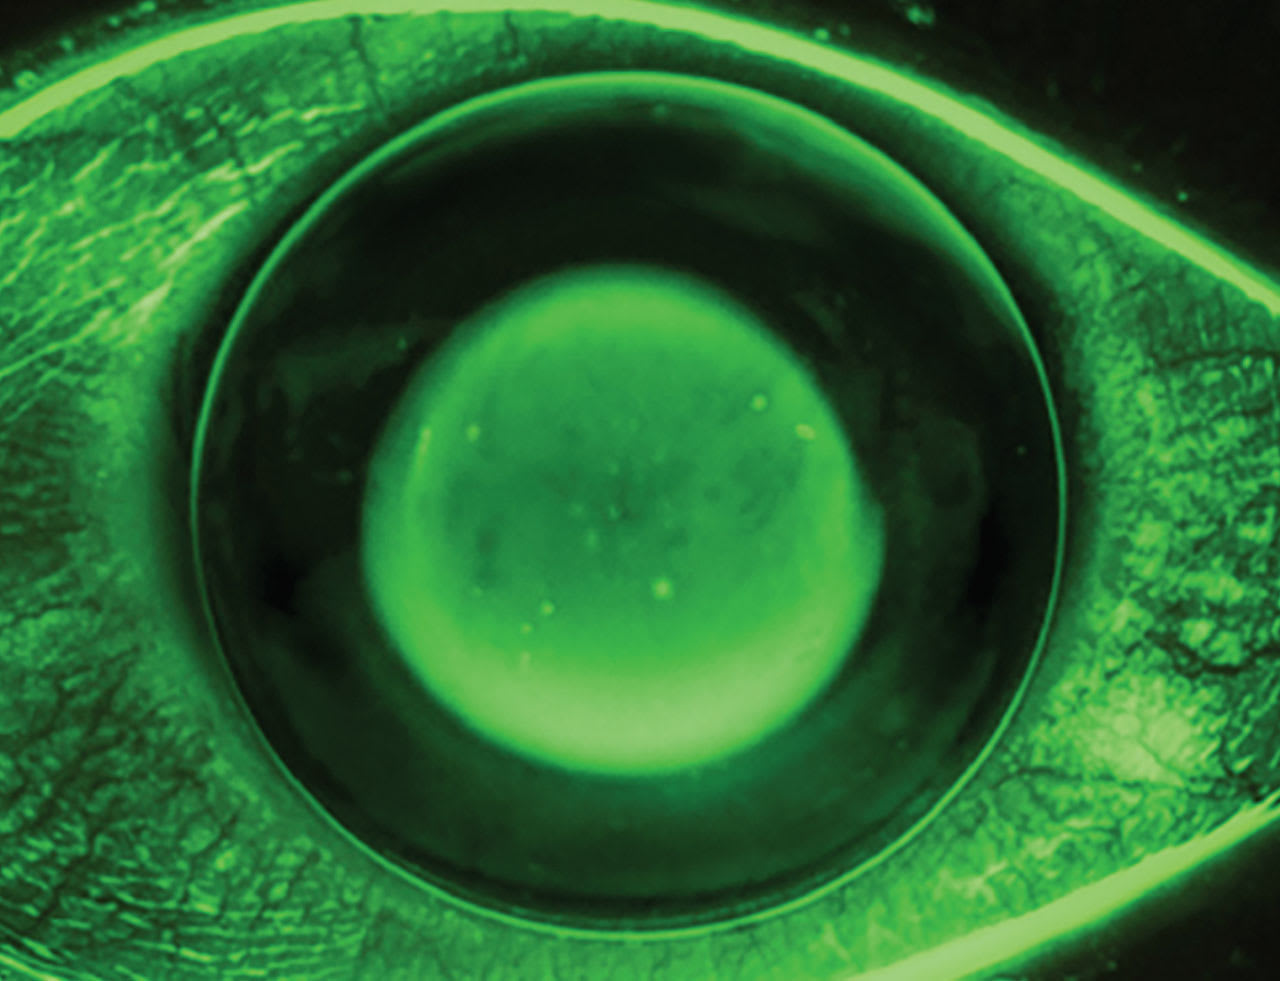

While scleral and ortho-k lenses with excessive edge lift can be problematic, so can those with tight-fitting relationships. Ortho-k lenses with alignment curves that are fit too steep to the peripheral cornea can create lens binding that leads to peripheral corneal staining and ocular discomfort. Understanding how the central lens–cornea relationship should look at dispense and follow-up visits can take some time to master. The dark central area of an ortho-k fit should appear defined, but the borders of the surrounding NaFl bull’s-eye will show some tear movement or exchange over the central cornea as the lens moves slightly on blink.

An ortho-k lens that is too shallow will resist exchanging the tear layer over the central cornea and cause central epithelial breakdown (Figure 2). A shallow lens may also show excessive edge lift, as the lens is bearing primarily on the central cornea. When edge lift is present, determine if the lens is too shallow or if the edges are too flat.

A lens that is too deep will show excess NaFl over the central cornea and is associated with a central island on topography. In this case, the patient will require more minus power in their manifest refraction than anticipated. Although it seems logical to flatten the base curve to correct the residual myopia, the correct remedy is to reduce sagittal depth to properly influence the epithelium. Deep lenses may also decrease tear exchange or show minimal edge lift (Figure 3).